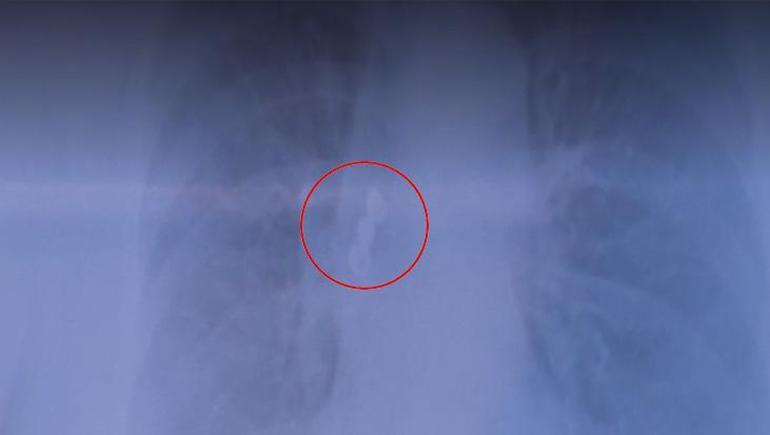

Kadın hastanın üst arka tarafta bulunan üçlü kaplama dişi akciğerine kaçtı. Sabah uyandığında dişlerinin yerinde olmadığını gören hasta acilen hastaneye başvurdu. Çekilen röntgen filminde dişlerin akciğerde olduğu görüldü. Hasta şanslıydı, çünkü soluk borusu tamamen tıkanabilirdi. Akciğerdeki diş bronkoskopi yöntemiyle çıkarıldı.

Göğüs Hastalıkları Uzmanı Prof. Dr. Levent Alpay, akciğer filminde üç dişten oluşan kaplama köprüsünün aspire edildiğini fark ettiklerini ve hastayı hemen yatırdıklarını söyledi. Sabah uyandığında dişlerinin yerinde olmadığını gören hastanın, dişleri yutmuş olabileceğini düşündüğünü belirten Alpay, bu tür durumlarda genellikle mideye kaçma ihtimalinin daha yüksek olduğunu vurguladı.

“Çekilen akciğer filminde kaplama dişin üç dişten oluşan kısmının aspire edildiğini görerek hastamızı hemen yatırdık.  Sabah uyandığında dişlerinin ağzında olmadığını gören hasta, “Acaba yuttum mu?” diye düşündü. Genelde bu tür durumlarda yutma söz konusu olur.